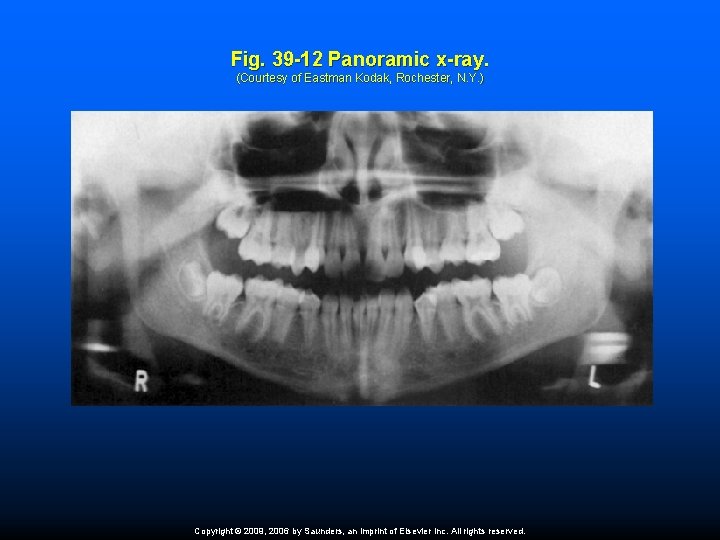

Extraoral Film An extraoral film is one that is placed outside the mouth during x-ray exposure. Extraoral films are used to examine large areas of the head or jaws. Examples of common extraoral films include panoramic and cephalometric films. A panoramic film shows a panoramic (wide) view of the upper and lower jaws on a single radiograph. A cephalometric film shows the bony and softtissue areas of the facial profile. Copyright © 2009, 2006 by Saunders, an imprint of Elsevier Inc. All rights reserved.

Fig. 39 -12 Panoramic x-ray. (Courtesy of Eastman Kodak, Rochester, N. Y. ) Copyright © 2009, 2006 by Saunders, an imprint of Elsevier Inc. All rights reserved.